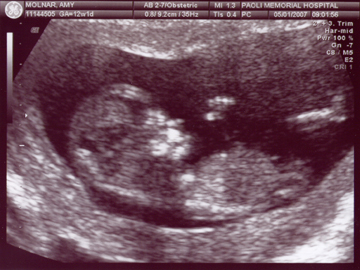

A good shot of her fingers